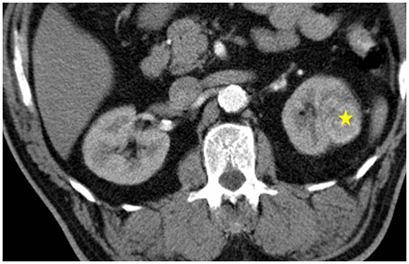

在電腦斷層導引下,將冷凍探針經過皮膚插到腫瘤組織中。冷凍探針在針尖可形成一圓型的超低溫範圍,當溫度低於-20℃即可造成細胞壞死,達到治療目的。因冰塊在電腦斷層下清晰可見,因此可確認治療範圍完全涵蓋腫瘤,且未傷害正常組織。冷凍治療具有包括侵入性極小,無痛,可保留腎功能等好處,於2006年通過衛生署認證,已證實為一安全有效的腎臟腫瘤治療方法。

2.以電腦斷層掃描確認治療位置。

4.在電腦斷層的導引下將冷凍探針插進腫瘤。